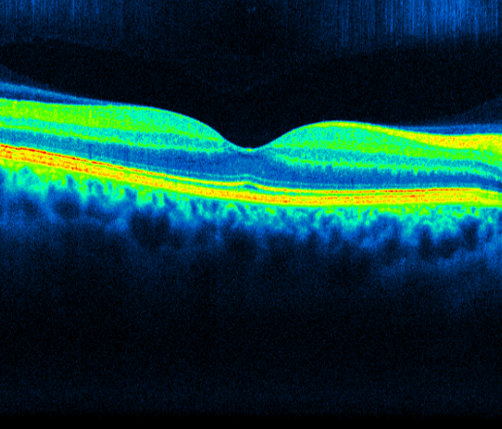

Focus on ... OCT